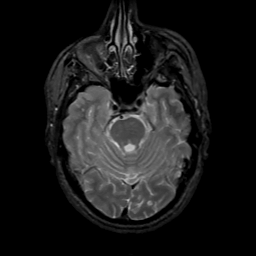

MR Study #7, March 24, 1991 -- Slice #15

[Home][Help][Clinical][Tour 1][Tour 2] Slice 15